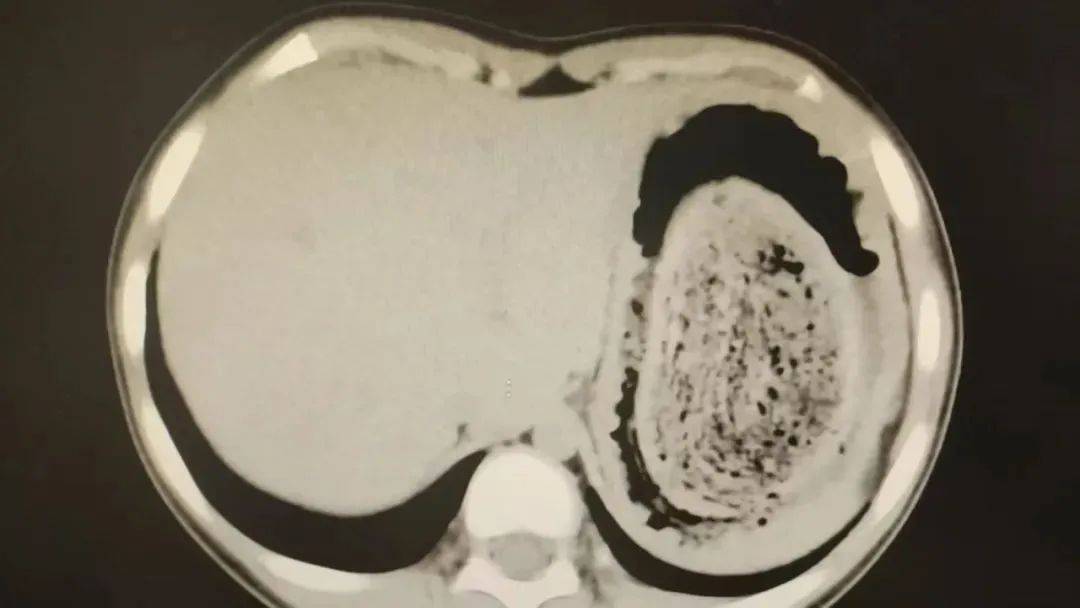

结果出来时,医生都惊呆了:小可的胃里,塞满了成团的头发,几乎占了胃容量的四分之三皇冠信用网账号申请。大量不能消化的物质,在胃酸的作用下发生变性,并与食物及其他物质结合形成团块,慢慢变成坚硬的“胃石”。

为了避免用手术方式去除头发团, 陈攸涛先让小可喝可乐软化“胃石”,再通过胃镜辅助取出头发,整个过程花了十几个小时,清理出的头发装了 两大盆皇冠信用网账号申请。

2024年10月,11岁女孩欢欢(化名)因腹痛难耐紧急送到医院,而就在两个月前,欢欢的父母发现她在拔自己的头发,偷偷吃掉皇冠信用网账号申请。经检查,医生发现她胃腔和肠管里有大块的毛絮状结石,几乎占据整个胃部。最终,一块长38厘米、宽15厘米、厚10厘米的毛发结石被取出。